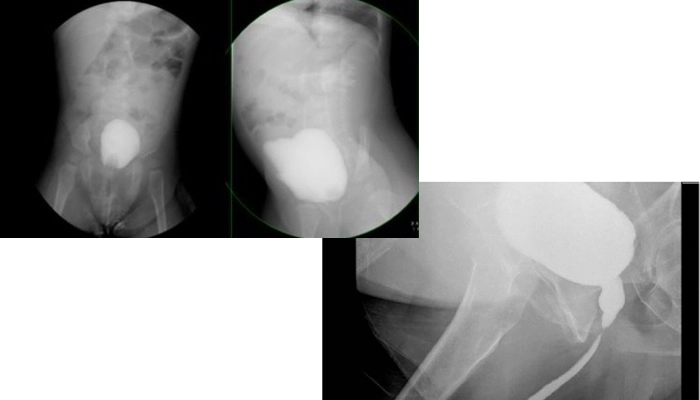

سیستواورتروگرام یا VCUG (Voiding Cysto Urethro Graphy) یکی از روشهای تصویربرداری پزشکی است که برای بررسی عملکرد مثانه و مجرای ادرار استفاده میشود. در این روش با کمک ماده حاجب و تصویربرداری با اشعه ایکس، وضعیت جریان ادرار و شکل دستگاه ادراری بهطور دقیق دیده میشود. پزشکان از VCUG برای تشخیص مشکلاتی مثل ریفلاکس ادراری (بازگشت ادرار به کلیهها)، تنگی یا انسداد مجرای ادرار و بررسی عوارض عفونتهای مکرر ادراری استفاده میکنند.

فرآیند انجام VCUG ساده است اما ممکن است برای بیمار کمی نگرانکننده به نظر برسد. در این روش ابتدا یک لوله باریک و استریل به نام سوند از طریق مجرای ادرار وارد مثانه میشود. سپس ماده حاجب (Contrast) از طریق این سوند وارد مثانه میشود تا در تصاویر اشعه ایکس بهخوبی دیده شود. وقتی مثانه پر شد، از بیمار خواسته میشود که ادرار کند. در همین زمان تصویربرداری انجام میشود تا جریان ادرار و حرکت ماده حاجب در دستگاه ادراری دیده شود.